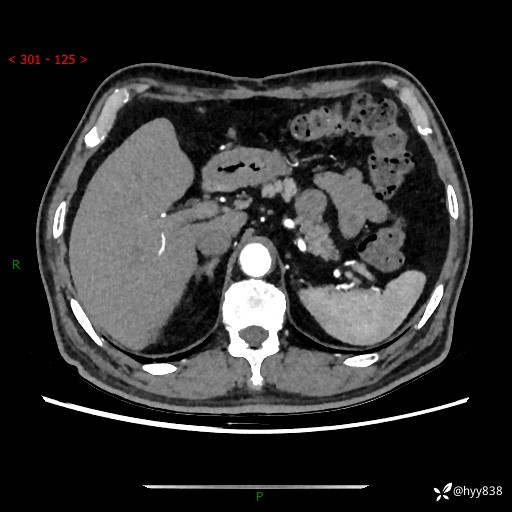

【检查】:胰腺CT平扫+增强